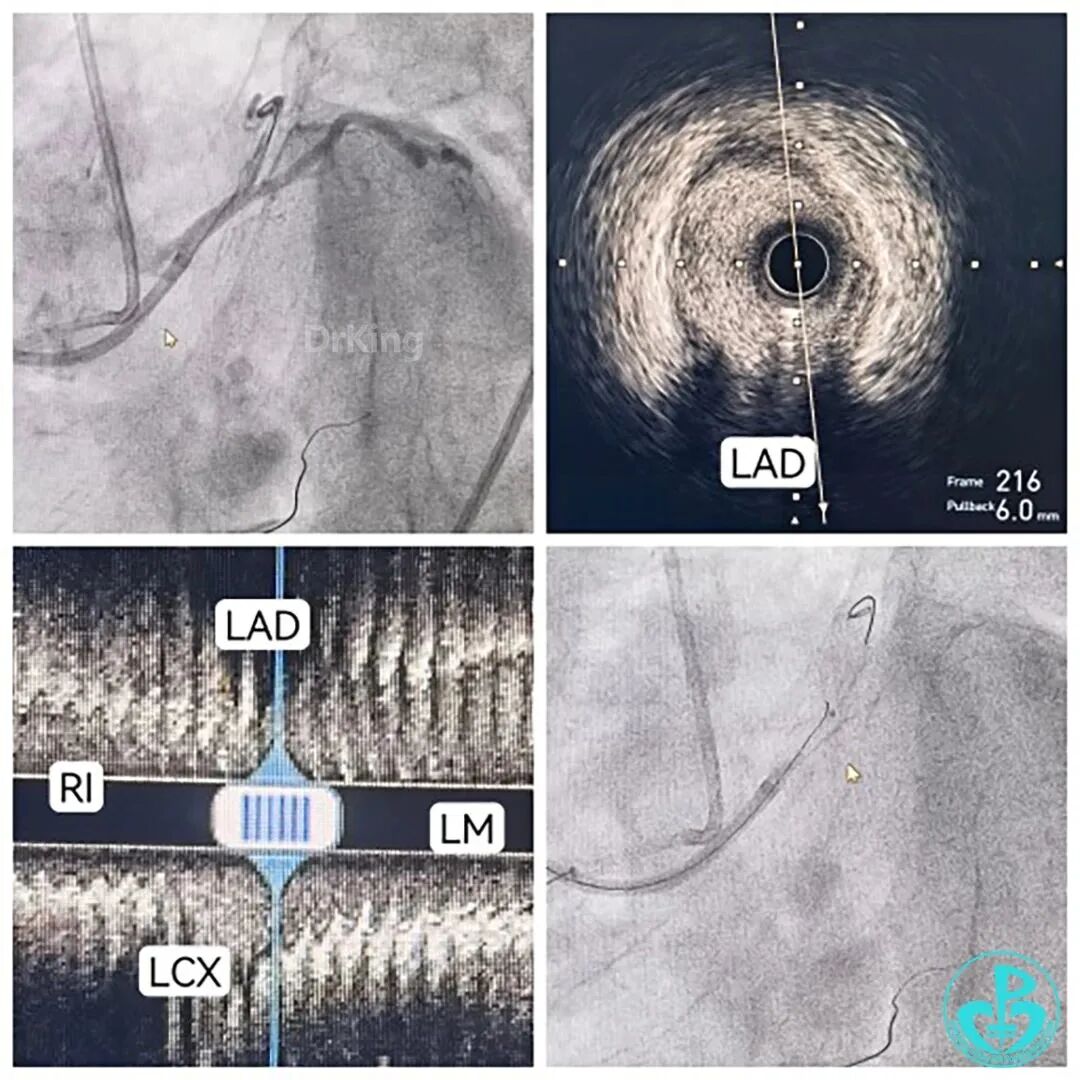

7F EBU 3.5导引导管置于左冠脉口部,导丝送至RI内,行IVUS检查:

1. 定位→LAD开口于LCX对侧略近处;

2. 定性→非纤维钙化残端,可见微通道;

3. 定策略:双腔微导管支撑+软导丝XTR先行试探。

导丝推进顺利,KDL交换为单腔微导管,逆向造影指引导丝送至LAD中远段真腔内,交换工作导丝,全程仅用了9分钟,IVUS精准、优化指导下PSP,DES 1枚,结果理想。